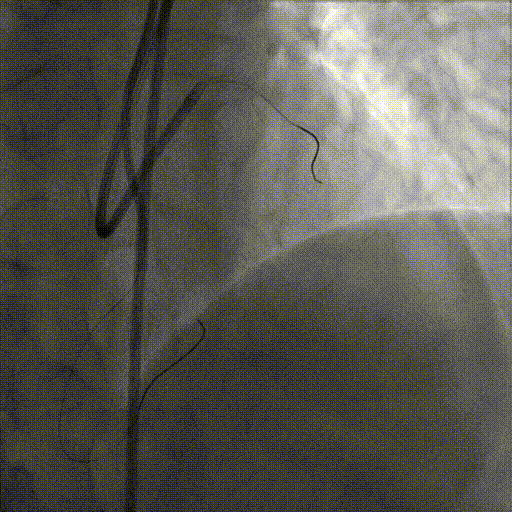

术前造影

术后造影